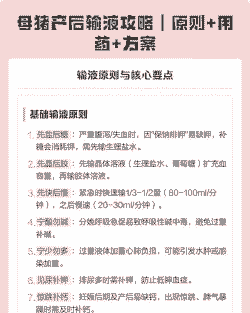

给产后母猪输液时,应遵循以下步骤和原则:

输液准备

输液顺序

输液速度

特殊情况的处理

监测与调整

注意事项: